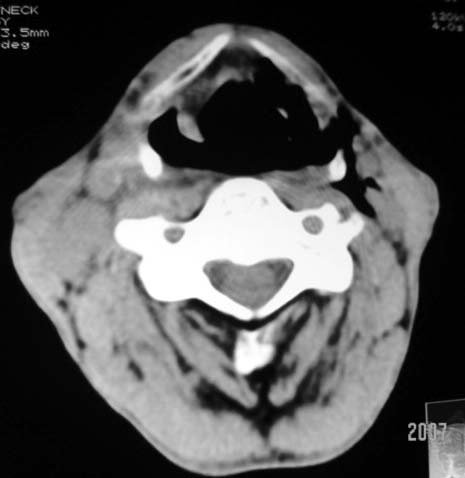

以下是引用dyqct在2007-4-20 16:19:00的发言:[br]考虑:1、左侧梨状窝区破裂伴左颈深、浅部气肿。[br] 2、右侧甲状腺区血肿(请追问病史是否伤及右颈部)。[br] 3、建议病情稳定后增强扫描除外右侧甲状腺腺瘤。